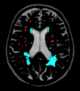

Deep white matter ischemia